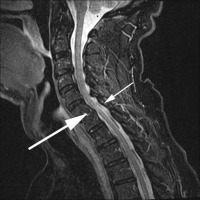

What is interesting is that a cervical degenerative spondylolisthesis tends to occur above and below very degenerative discs. That is, the discs below this slip level have become so degenerative that they are relatively immobile. This increases the stress on the facets above the degenerative disc levels and wears them out prematurely. See the accompanying image (image 3) to understand this concept.

The forward slip of the upper vertebra on the lower one has ramifications for the diameter of the spinal canal. Since the canal is a series of concentric rings piled perfectly one on top of another, the forward slide of the upper vertebra can significantly narrow the canal and potentially compress the spinal cord.

Because the volume of the canal, with or without this pinching will enlarge with forward bending and decrease in size with backward bending, you can imagine what happens to the canal that is already narrowed when you add backwards bending. This narrowing of the canal can cause compression of the cord and a condition called myelopathy-dysfunction of the spinal cord. See this website for a description of these symptoms.